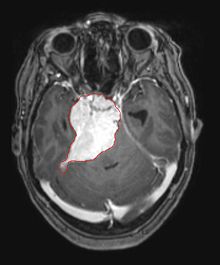

Les méningiomes sont les tumeurs cérébrales extrinsèques ou extra-axiales intracrâniennes les plus courantes qui proviennent des cellules de l'arachnoïde, la membrane qui recouvre le cerveau et la moelle épinière. L'incidence de cette néoplasie est d'environ 2 cas par an pour 100 000 habitants. Ils sont plus fréquents chez les femmes dans leurs sixième et septième décennies. Leur fréquence est plus élevée chez les patients atteints de neurofibromatose de type 2. La perte du chromosome 22 est caractéristique des méningiomes, bien que la signification pronostique de cette découverte soit encore incertaine.

Les patients atteints de méningiome peuvent présenter des symptômes typiques d'une lésion crânienne massive, notamment des convulsions et des déficits neurologiques focaux. détecté sur la tomodensitométrie et l'imagerie par résonance magnétique pour d'autres raisons. Cette tumeur de résonance a un aspect caractéristique, consistant généralement en un rehaussement de contraste uniforme le long de la dure-mère avec une séparation nette du parenchyme cérébral. Une autre caractéristique, bien que non présente dans tous les cas, est la soi-disant "queue durale", représentée par un renflement qui s'étend au-delà de la lésion et indique le point d'ancrage dans la dure-mère.

De nombreux méningiomes découverts fortuitement ne nécessitent pas de traitement au moment du diagnostic initial. Si le patient présente un effet de masse significatif, que les symptômes soient présents ou non, le traitement de choix est généralement complet résection. Dans un studio Mayo Clinics comparant les taux de contrôle des tumeurs après résection chirurgicale et radiochirurgie chez des patients atteints de méningiome intracrânien petit à modéré et sans symptômes d'effet de masse, la radiochirurgie a permis un meilleur contrôle (98 contre 88 %) et avec moins de complications (10 contre 22 %) par rapport à l'ablation chirurgicale.